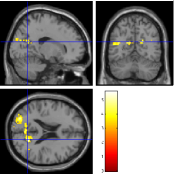

Once the reduced FOV images are available, the proposed pMRI 4D-UWR-SENSE algorithm and its early UWR-SENSE version have been utilized in a final step to reconstruct the full FOV EPI images and compared to the mSENSE Siemens solution. For the wavelet-based regularization, dyadic Symmlet orthonormal wavelet bases [48] associated with filters of length 8 have been used over resolution levels. The reconstructed EPI images then enter in our fMRI study in order to measure the impact of the reconstruction method choice on brain activity detection. Note also that the proposed reconstruction algorithm requires the estimation of the coil sensitivity maps (matrix in Eq. (2)). As proposed in [4], the latter were estimated by dividing the coil-specific images by the module of the Sum Of Squares (SOS) images, which are computed from the specific acquisition of the -space centre (24 lines) before the scans. The same sensitivity map estimation is then used for all the compared methods. Fig. 5 compares the two pMRI reconstruction algorithms to illustrate on axial, coronal and sagittal EPI slices how the mSENSE reconstruction artifacts have been removed using the 4D-UWR-SENSE approach. Reconstructed mSENSE images actually present large artifacts located both at the centre and boundaries of the brain in sensory and cognitive regions (temporal lobes, frontal and motor cortices, …). This results in SNR loss and thus may have a dramatic impact for activation detection in these brain regions. Note that these conclusions are reproducible across subjects although the artifacts may appear on different slices (see red circles in Fig. 5). One can also notice that some residual artifacts still exist in the reconstructed images with our pipeline especially for . Such strong artifacts are only attenuated and not fully removed because of the high level of information loss at .

| mSENSE | 4D-UWR-SENSE | ||

| Axial |  |

|

|

| Coronal | |||

| Sagittal | |||

| Axial |  |

|

|

| Coronal | |||

| Sagittal |